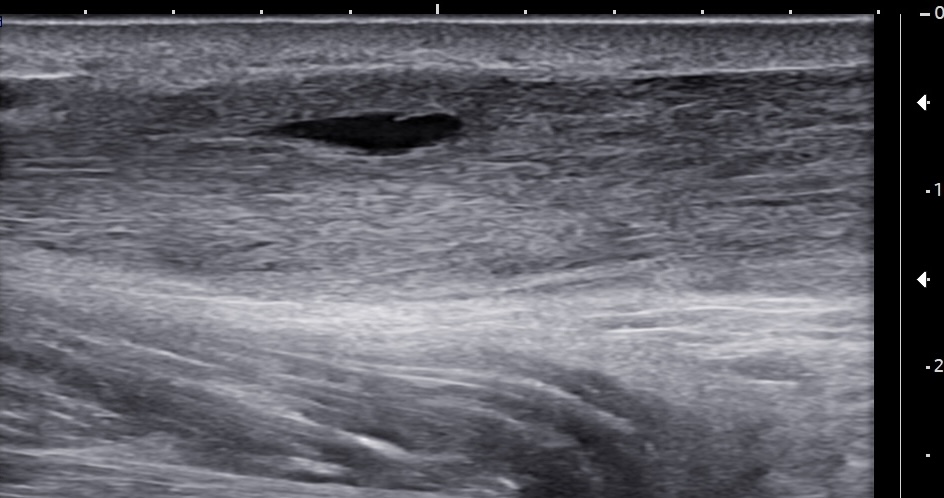

Short-axis ultrasound image of the midportion Achilles tendon showing the tendon thickness measurement.

Unlabeled short-axis ultrasound image of the midportion Achilles tendon.